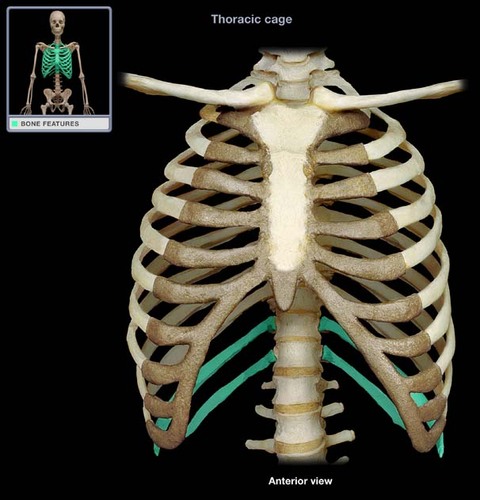

floating ribs

costal cartilage